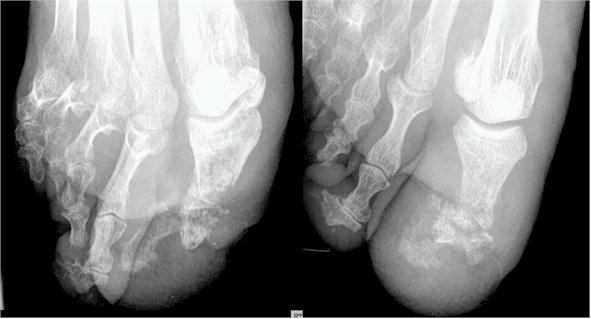

Røntgenbildet av denne pasientens høyre fot bekreftet mistanken om en dyperegående infeksjon med ødeleggelse av benvevet (osteomyelitt).

Røntgenbilde av osteomyelitt - infeksjon i benPasienten ble innlagt på sykehus med tanke på antibiotikabehandling og sannsynligvis også amputasjon av det døde vevet i stortåen for å forhindre videre utbredelse av infeksjonen.